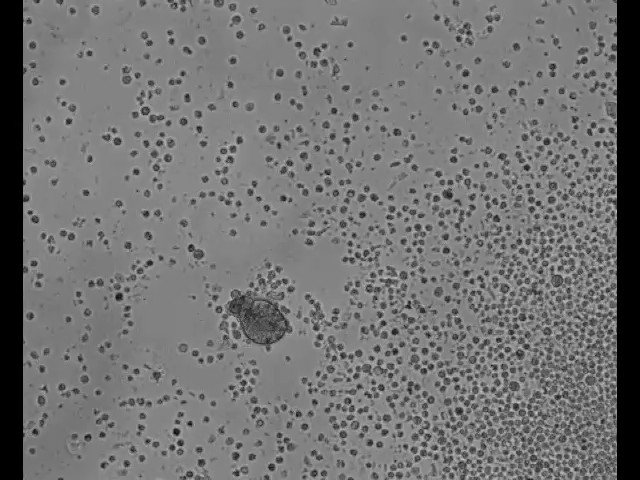

What is this? A primitive pond organism? nope, #Anthrobots

tiny robots made of human cells that can repair damaged neural tissue. These robots, called #anthrobots, are composed of human tracheal cells and are able to move and self-assemble, making them ideal candidates for delivering therapeutic agents to specific locations in the body.